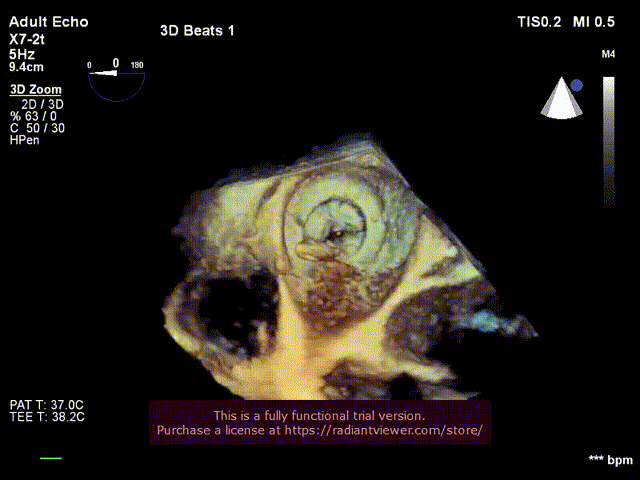

1.食道超声引导房间隔穿刺(经电刀辅助)

房间隔穿刺“小帐篷征”

房间隔穿刺成功

三维显示二尖瓣形态及房间隔穿刺鞘

6.经食道超声评估主动脉瓣位SAPIEN 3植入

位置良好,瓣叶运动良好,无反流